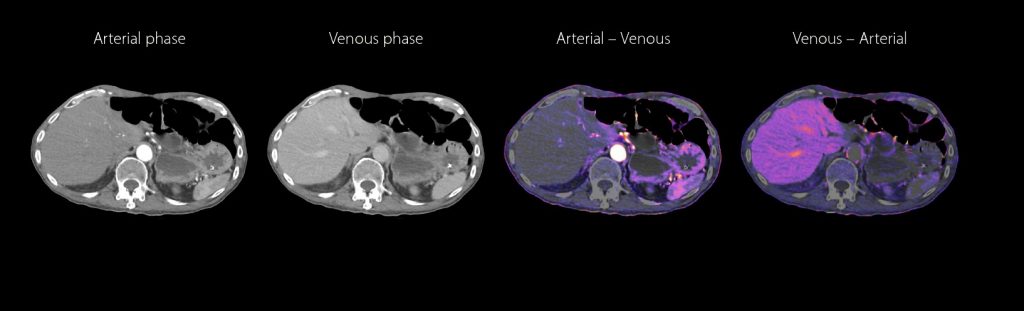

ONCOLOGY IMAGING

Aquilion Prime SP empowers your ability to detect, stage and track tumors with color iodine maps* available for every routine multi-phased liver exam.